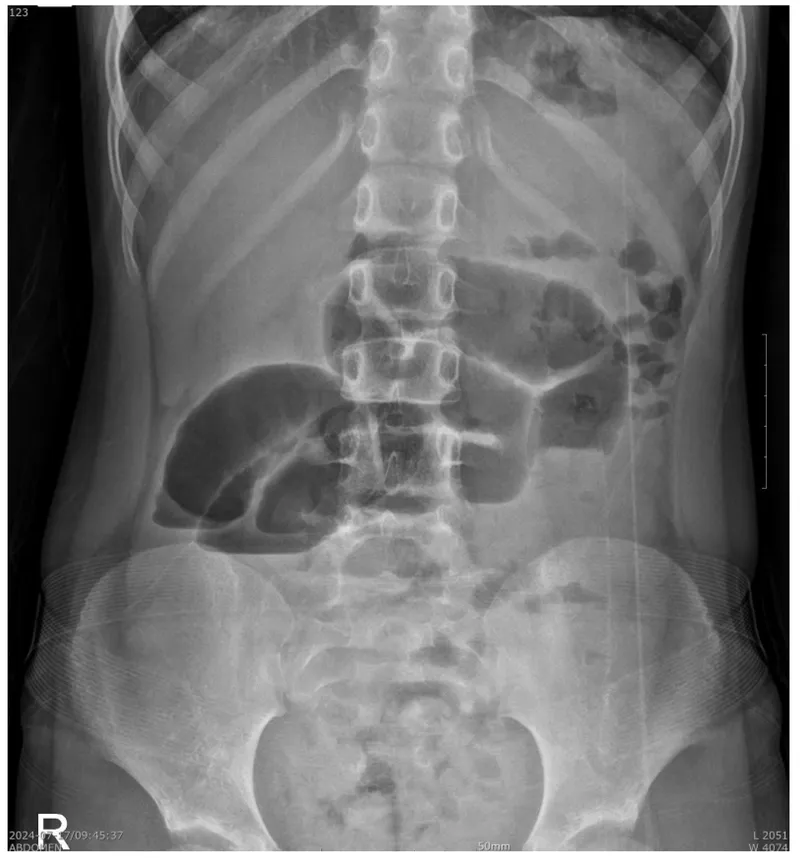

Postoperative Ileus (POI): A common, temporary impairment of gastrointestinal motility following surgery, leading to a functional (non-mechanical) obstruction.

- Symptoms: Nausea, vomiting, abdominal distension, inability to tolerate oral diet, absent flatus or bowel movement.